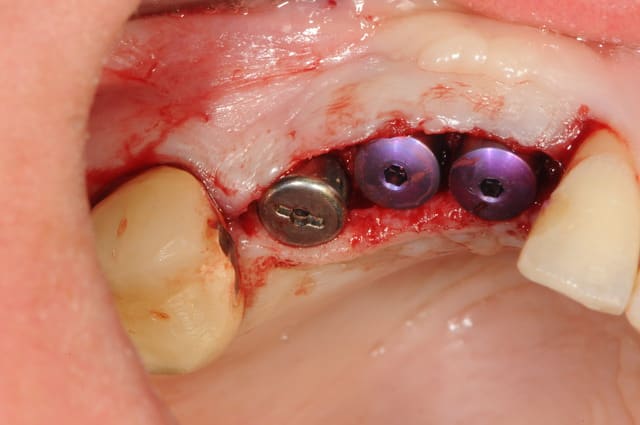

Pour ton anniv pluton je mets un cas identique.

j'ai 6 mois d'avance sur toi dudule

un cas dont j'avais discuté ailleurs avec amibien qui m'avait reproché de ne pas avoir fait la pose en même temps en juin dernier

la pose est de jeudi dernier mon apn est en panne, photo avec le portable, desolé pour le sang mais quand cela saigne il n'y a pas d'échec

il se trouve que j'aimerais utiliser ces photos car c'est le nouveau systeme d'implants, et je n'ai encore pas d'autres cas de fracture en cours

enfin si mais pas aussi belle

j'ai donc agrandi la zone est ce qu'un pro de la photo peut faire mieux?

pour dudule, je ne fais pratiquement jamais de décharge en distal

pour pluton, je viens de poser les implants le cas n'est pas fini